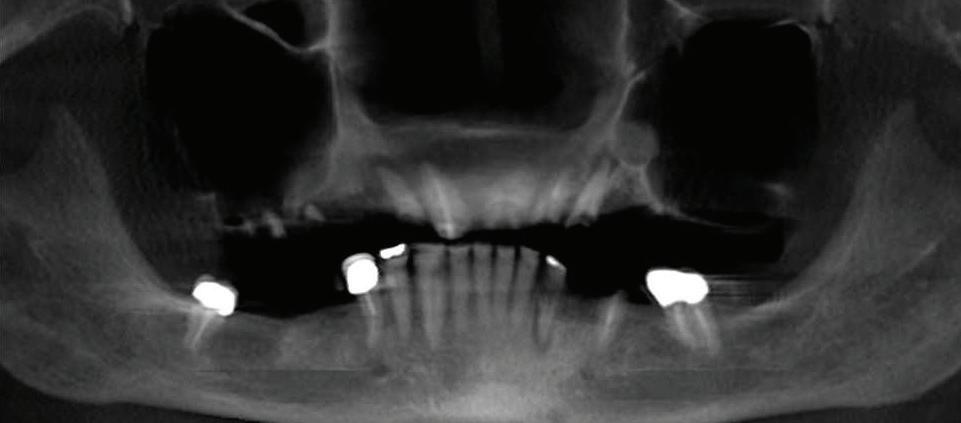

At Elite Prosthetic Dentistry, our “dream team” delivers an extraordinary blend of clinical precision and genuine care. Led by Gerald M. Marlin, D.M.D., M.S.D., a renowned specialist with over 3,700 successful implant procedures and a history of crafting crowns that last over 35 years, we are the trusted choice for adults seeking implant, cosmetic, and reconstructive dentistry in the Washington, DC metropolitan area. Why Choose Elite Prosthetic Dentistry?

• Expertise in saving teeth, problem-solving failing restorations, and addressing TMJ issues. Proven success in implant therapy, offering long-term results with minimal bone loss.

• Comprehensive care, including surgical implant placement, bone grafting, and custom restorations—all performed in our state-of-the-art office.

• An in-house laboratory ensuring efficiency and precision for veneers, crowns, and implant restorations.

• A warm, caring environment supported by a highly skilled team with an average tenure with us of 14+ years, complemented by oral and IV sedation protocols. With a commitment to advanced digital technology and artistry, Dr. Marlin works closely with each patient to deliver “simply radiant, simply natural” results. Our crowns last more than three times the national average, and our implants boast a >97% success rate over 20 years. Your journey to a revitalized smile begins here. Contact us today to schedule your consultation and experience the difference of truly exceptional dental care.